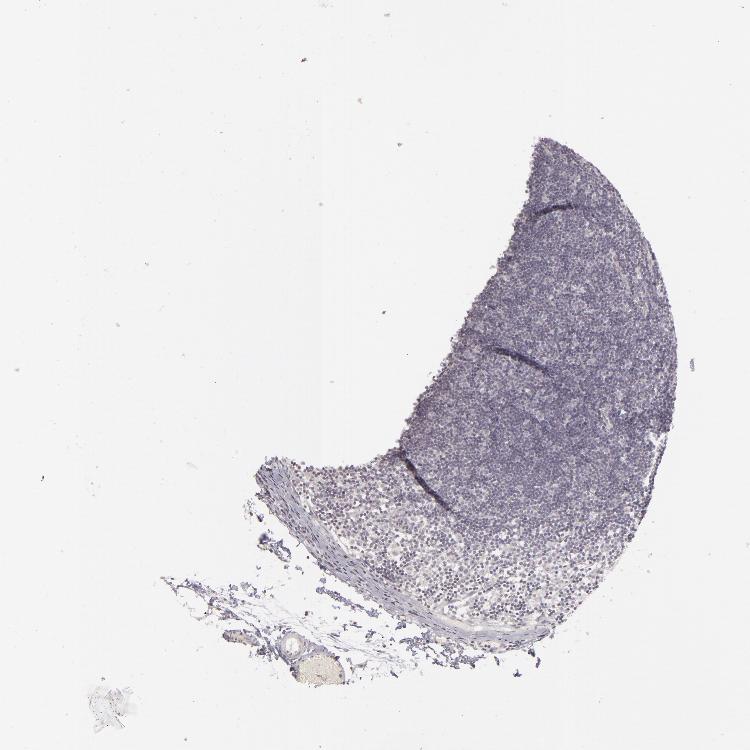

TISSUE PRIMARY DATA LYMPH NODE Show tissue menu

Lymph node

LYMPH NODE - Antibody stainingi

Antibody staining in the annotated cell types in the current human tissue is reported as not detected, low, medium, or high, based on conventional immunohistochemistry profiling in selected tissues. This score is based on the combination of the staining intensity and fraction of stained cells.

Each image is clickable and will lead to virtual microscopy that enables deeper exploration of all samples and also displays staining intensity scores, fraction scores and subcellular localization as well as patient and tissue information for each sample.

Antibody HPA001893Antibody CAB058690

Germinal center cells Not detectedNot detected

Non-germinal center cells LowNot detected